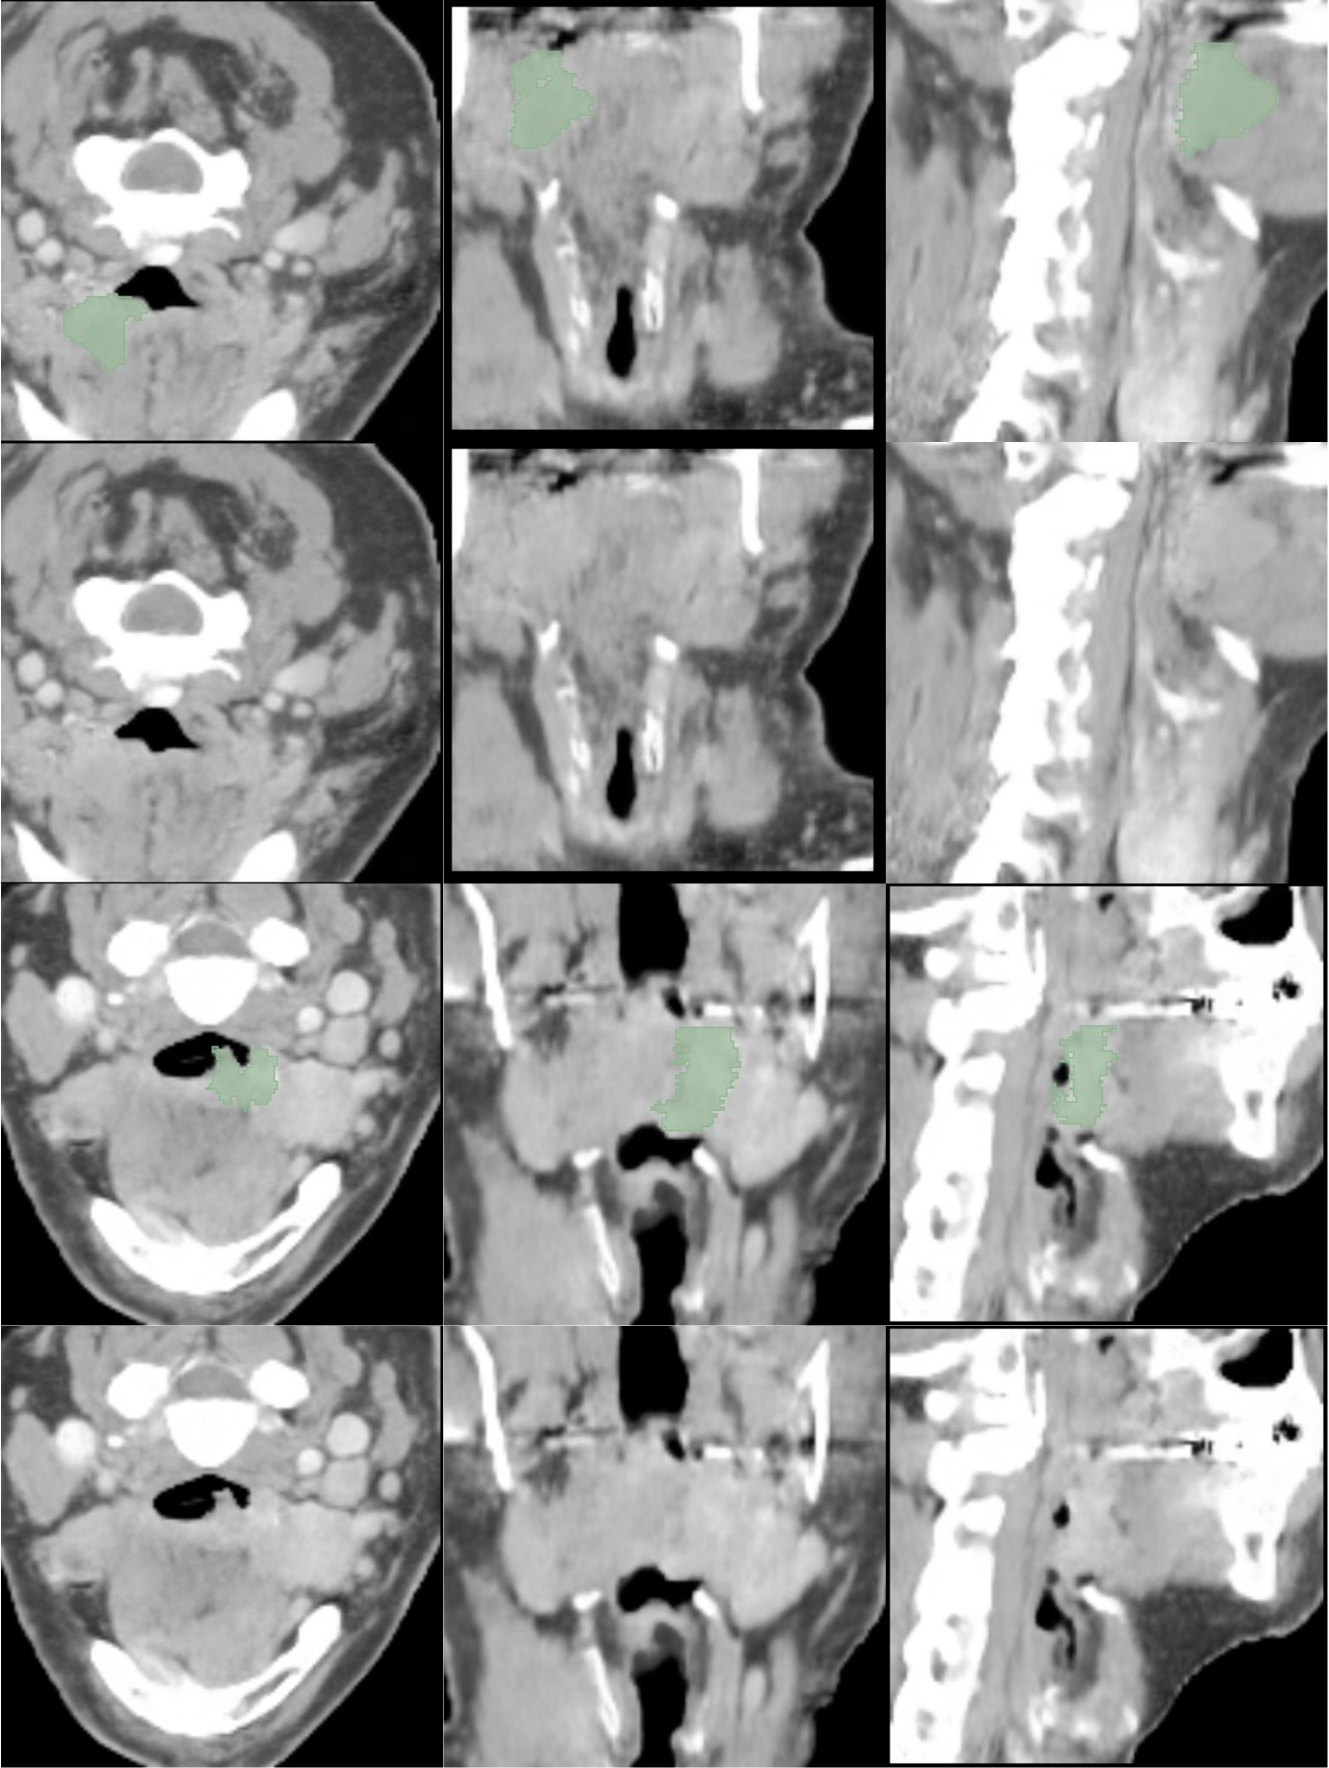

In G (Figures 17, 18, 19 and 20) and H (Figures 21, 22 and 23) are presented CT and MRI synthetic cases with the respective tumor segmentations.

Figures 24, 25 and 26 in I present synthetic CT cases with the respective predictions of TotalSegmentator, TotalSpineSeg and AMASSS-CBCT.